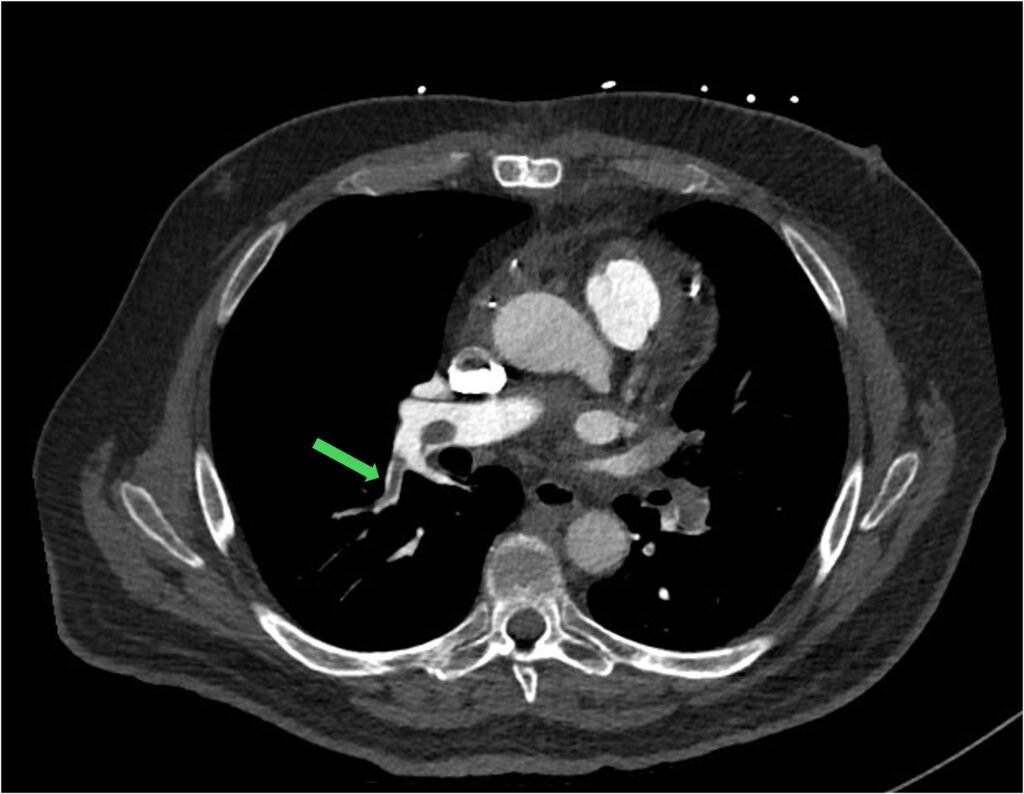

Sometimes the formation of clots is so extensive, you can see a saddle shape clot within the bifurcation of the pulmonary trunk. This (saddle PE) is often associated with high clot burden and RV strain.

Figure 6: saddle PE (green arrow)